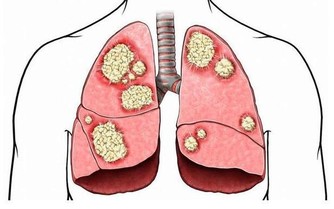

醫學上,胰腺癌是一種惡性程度很高,診斷和治療都很困難的消化道惡性腫瘤,約90%為起源於腺管上皮的導管腺癌。其發病率和死亡率近年來明顯上升。5年生存率<1%,是預後最差的惡性腫瘤之一,正因如此,人們將其稱為癌症之王!胰腺癌早期的確診率不高,手術死亡率較高,而治愈率很低。本病發病率男性高於女性,男女之比為1.5~2:1,男性患者遠較絕經前的婦女多見,絕經後婦女的發病率與男性相仿。

其實胰腺癌早期症狀非常隱匿,可能只是輕微的腹痛腹脹,很多患者常常把胰痛當做胃痛,直到出現很嚴重的症狀時,才會來醫院就診,可是往往已喪失手術機會。